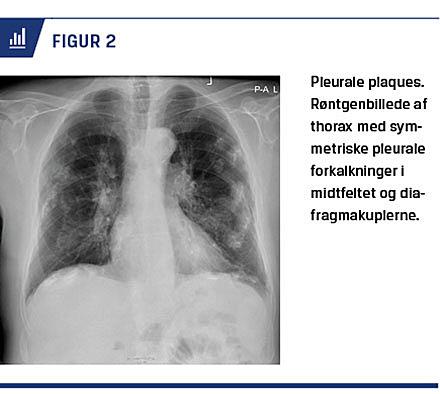

Pleurale plaques forekommer hyppigt blandt tidligere asbesteksponerede, og de kan ses efter forholdsvis beskeden eksponering [10]. Pleurale plaques påvises ofte tilfældigt i forbindelse med røntgenfotografering af thorax. Pleurale plaques er normalt en benign asymptomatisk manifestation, der udtrykker, at man har været udsat for asbest. Pleurale plaques kan i sjældne tilfælde, hvor de er udbredt som et panser, være associ-eret med nedsat FVC og dyspnø [7, 11]. Rygning øger ikke risikoen for pleurale plaques [7]. Patologisk drejer det sig om multifokal og bilateral fibrose i pleura pari-etalis, der dannes efter en inflammatorisk reaktion, og som sjældent viser sig før 20 år efter asbestudsættelsen [7]. Forandringerne kan kalcificere og progrediere efter eksponeringsophør [7]. De pleurale plaques sidder typisk over diagfragmakuplen, i den mediastinale pleura eller følger costa 6-9 lateralt og bagtil [7, 8]

(Figur 2).